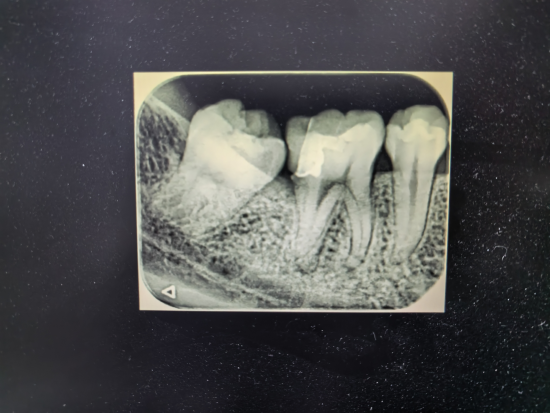

为进一步精准评估患牙情况,诊疗过程中需拍摄根尖片。哈医大一院口腔放射线科配备了低剂量根尖片投照设备,并为患者提供了全身防护铅衣,可最大程度降低辐射风险,保障孕期诊疗安全。在黄鑫医生的细致操作与全程安抚下,顺利为李女士的右下第一磨牙实施开髓、根管预备及氢氧化钙暂封治疗。治疗后,李女士的牙痛症状明显减轻,终于能摆脱疼痛,安心养胎。